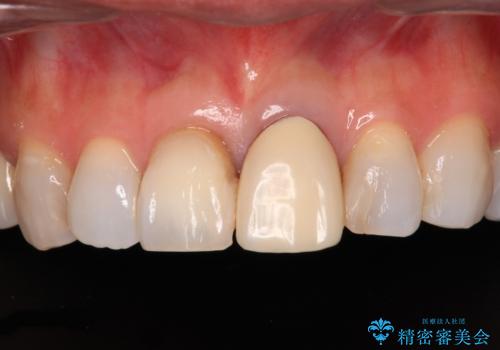

- 変色した保険の前歯のクラウンを交換したいとのことで来院された患者様です。

中心左側の歯はクラウンが装着されており、右側は神経組織が除去されて多少変色している状態でした。

右側の歯も将来的にもっと変色する可能性があるため、前歯2本をオールセラミッククラウンにて補綴治療を行うこととしました。